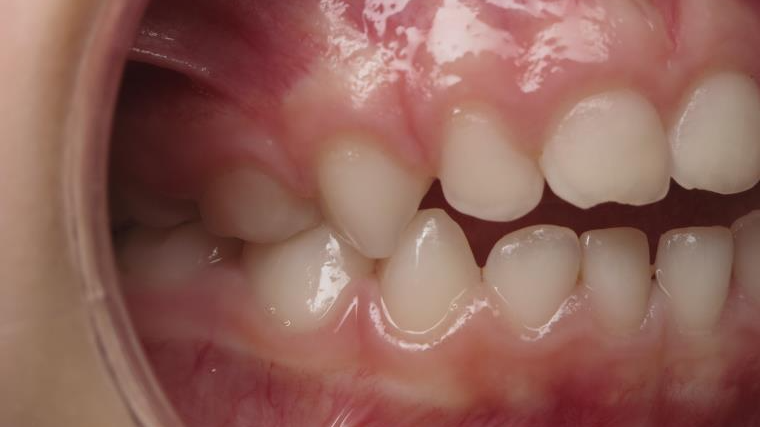

sectionnel multibagues pendant 8 mois

surveillance évolution de la dentition en cours